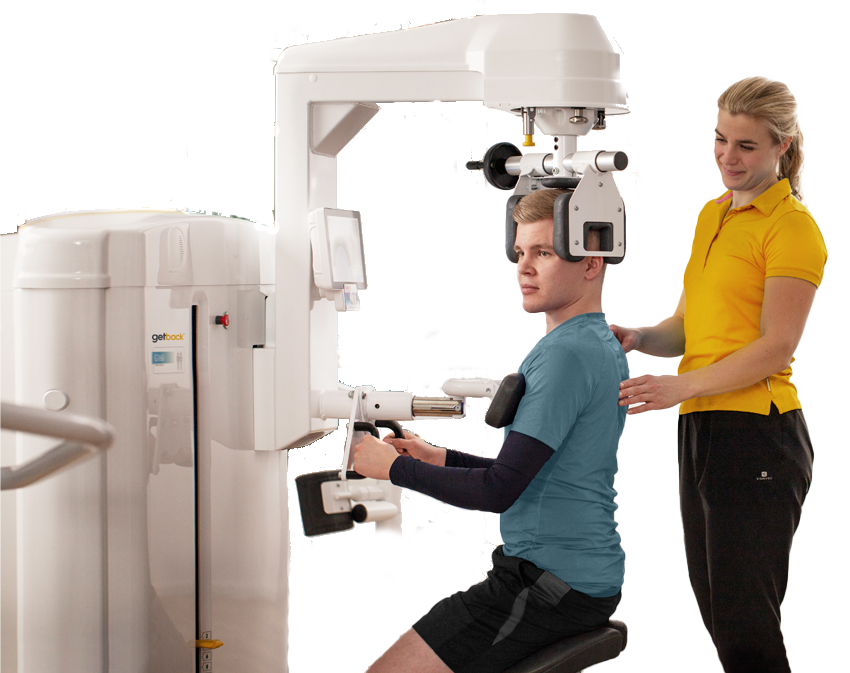

Read moreGETBACK™ Your Pathway to Spinal Health!

At SAOC, we bring you the latest advancements in spinal health. We are excited to introduce getback™ at Berwick. This physiotherapy-based program helps re-activate and strengthen deep spinal muscles linked[…]